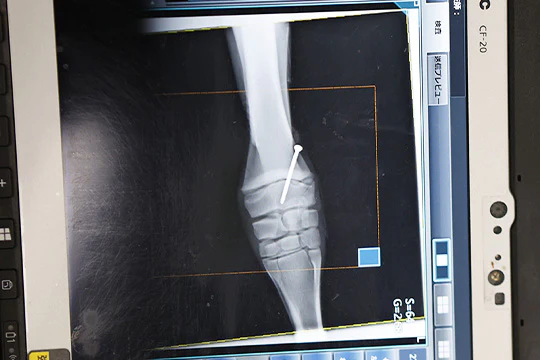

取材時に来院した子馬の肢軸矯正に関する手術の様子

成長期整形外科疾患Developmental Orthopedic Disease (DOD) の一つである肢軸異常Angular Limb Deformity(ALD)を発症している子馬に対し、これを矯正する手術を実施。①歩様検査で左前肢がO脚状に曲がっているのを確認、②麻酔→成長を抑制したい側の成長版に、③裸子を挿入して、④麻酔が覚めたら起立を補助して終了。裸子は肢が真っ直ぐに伸びたら抜去します。このような肢軸異常は将来的な競走能力に悪影響を及ぼす可能性があるため、骨の成長板が残っているうちに矯正されるのが一般的です。